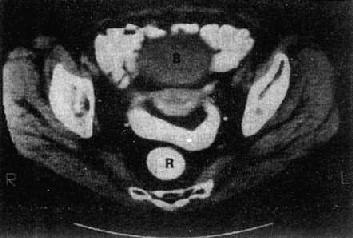

子宫体在CT上易于识别,显示为横置的密度较高的梭形影像,CT值40~80Hu,宫体中央密度可略低。子宫大小受年龄和生理状态的影响,一般成人前后径为1.5~3cm,左右径为3~5cm,老年人子宫较小。膀胱充盈程度也影响子宫的大小。子宫前方为膀胱,呈液性低密度;后方为直肠,内常有气体。膀胱、子宫、直肠之间常有肠袢存在。宫颈在宫体下方层面,呈卵圆形软组织影。卵巢位于子宫侧壁和臼内壁之间,正常大小时CT常不见。增强扫描,子宫密度均匀增加,膀胱内造影剂为高密度,盆腔内血管输尿管显示为高密度,易于识别(图4-5-5)。

图4-5-5 女性盆腔正常CT表现

子宫呈横行的梭形软组织影(↓),其前方为膀胱(B)

其后方、骶骨之前为直肠(R)